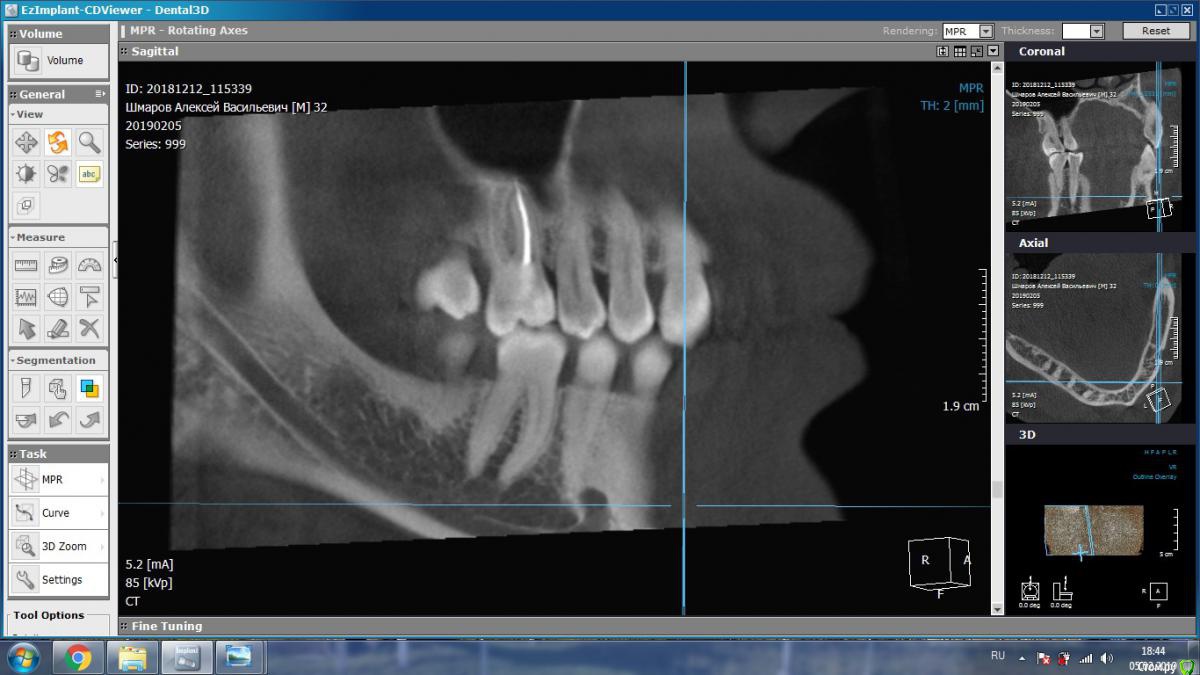

aleks.k Опубликовано 6 февраля, 2019 Автор Поделиться Опубликовано 6 февраля, 2019 Срезы Ссылка на комментарий

aleks.k Опубликовано 6 февраля, 2019 Автор Поделиться Опубликовано 6 февраля, 2019 Еще один срез, может быть более удачный чем первые в этой проекции Ссылка на комментарий

DmitrySH Опубликовано 6 февраля, 2019 Поделиться Опубликовано 6 февраля, 2019 Срезы Очень хорошо. Теперь как первые три, но увеличить 16 зуб. Остальные нам мало интересны, пазуха тоже Ссылка на комментарий

DmitrySH Опубликовано 7 февраля, 2019 Поделиться Опубликовано 7 февраля, 2019 В шестом зубе похоже еще 1 канал есть Ссылка на комментарий